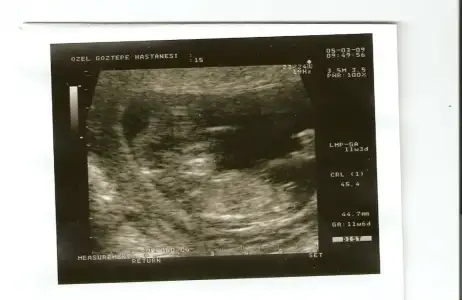

anaa hakkaten besbelli.masallah senınkı baya baya erkek olucak:roflol:kızlar burda bebişim 11+3 ken.ve bacak arasındaki çıkıntıya bakın:) doktor erkek demişti.

kızlar burda bebişim 11+3 ken.ve bacak arasındaki çıkıntıya bakın:) doktor erkek demişti.

valla göremedim bitanem ya.aa hayrlı uğurlu olsun sağlıkla gelsin bebişin.bu arada kartal dimi senin ikamet canım?kızlar burda bebişim 11+3 ken.ve bacak arasındaki çıkıntıya bakın:) doktor erkek demişti.

ya bı daha baktım da ecem,o parmakları mı pipisi mı

doktor pipisi dedi.ama bazı kızlarda da dudak şiş oluyormuş benzetebiliyorlarmış..bu cuma daha büyümüş haliyle kesin cinsiyetini dicek doktor..o zaman koyarım gene bebişi..

kızlar burda bebişim 11+3 ken.ve bacak arasındaki çıkıntıya bakın:) doktor erkek demişti.

kızlar burda bebişim 11+3 ken.ve bacak arasındaki çıkıntıya bakın:) doktor erkek demişti.

tatlım ne kadar bariz belli maşallah valla ogluşuna

kızlar burda bebişim 11+3 ken.ve bacak arasındaki çıkıntıya bakın:) doktor erkek demişti.

canim yaa bence o bebisin eli.kol kemigini takip et bak bi..hayirlisi olsun insallah.bana eliymis gibi geldi.CADIARZUcünkü o kadar büyük olmuyo benimde oglum olcak hayirlisiyla ordan biliyorum azicik yani.